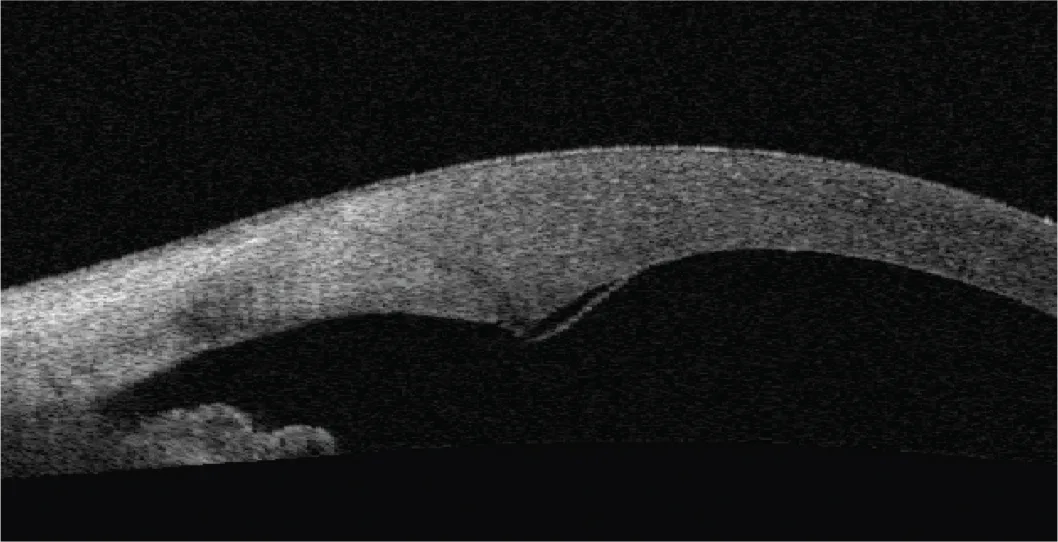

Figure 3.4. Coupe OCT à J1 montrant un œdème des berges ainsi qu’un descemetocèle au niveau de l’incision principale (1,2 mm).

Figure 3.6. Deux constructions incisionnelles différentes en OCT HD : incision directe (2,75 mm) mais tunnelisée (A)

Figure 3.6. Deux constructions incisionnelles différentes en OCT HD : et incision construite (1,8 mm) en trois plans (B).

Figure 3.7. OCT peropératoire de l’incision principale (2,2 mm), juste après réalisation de celle-ci (A)

Figure 3.7. OCT peropératoire de l’incision principale (2,2 mm), et en fi n d’intervention après l’implantation (B).